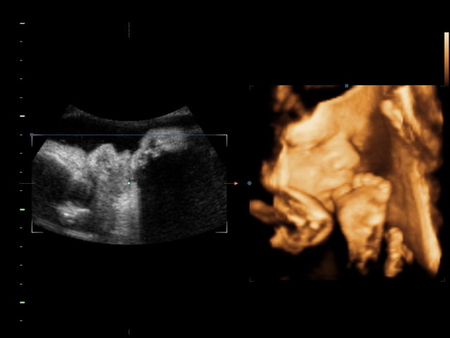

Я со своим ходила, если не ошибаюсь в 31 или 32 недели - раньше не получалось, было все так здорово видно, правда сынок спал и сосал пальчик на ножке) вот фото

по-моему где-то 31-32 недели, помню нам в одной клинике отказали делать 3Д, сказали, что после 29 недель уже ребеночек большой и будет плохо видно, но как оказалось-все было отлично видно и интересно)))